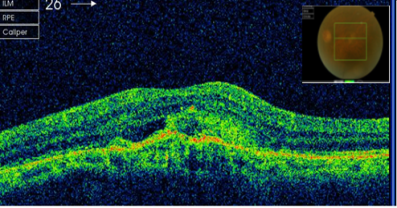

患者曹某,80岁,因双眼视力下降1年就诊。检查右眼视力0.3,左眼0.08,裂隙灯检查双眼晶体皮质混浊明显,散瞳后眼底检查见右眼黄斑区金箔样反光,左眼黄斑区中心凹反光消失。患者眼底荧光照影检查显示左眼黄斑区有血管荧光的渗漏,眼科光学相干断层扫描(OCT)检查显示右眼有黄斑前膜增生,左眼脉络膜新生血管膜(图片1)。诊断:左眼老年性黄斑变性(脉络膜新生血管),右眼黄斑前膜,双眼老年性白内障。患者于2013年3月行眼内注药(雷珠单抗)。3月后复诊左眼视力0.1,复查OCT示左眼视网膜新生血管膜消退(图片2),建议先行左眼白内障手术治疗。

图片2右眼黄斑前膜增生

老年性黄斑变性是老年人视力下降的常见原因之一,它是由于视网膜光感细胞代谢产物逐渐堆积形成玻璃膜疣,刺激脉络膜组织形成新生血管。本病如果不经治疗,最终新生血管膜形成瘢痕,导致视力重度永久性丧失。以往针对老年性黄斑变性(脉络膜新生血管)主要做光动力学疗法(PDT),PDT主要起到稳定视力的作用,很少能够提高视力。抗VEGF药物(如雷珠单抗)的问世是此类疾病治疗革命性的突破。由于雷珠单抗是通过眼内注射给药,而且价格昂贵,目前国内多数给药方案为每月一次,连续三个月,然后根据病情发展情况决定是否需要追加给药。该患者因经济因素仅一次给药治疗,但已能观察到明显的脉络膜新生血管消退。由于患者白内障比较明显,故推荐先行白内障手术,术后仍需定期观察决定后续治疗方式。